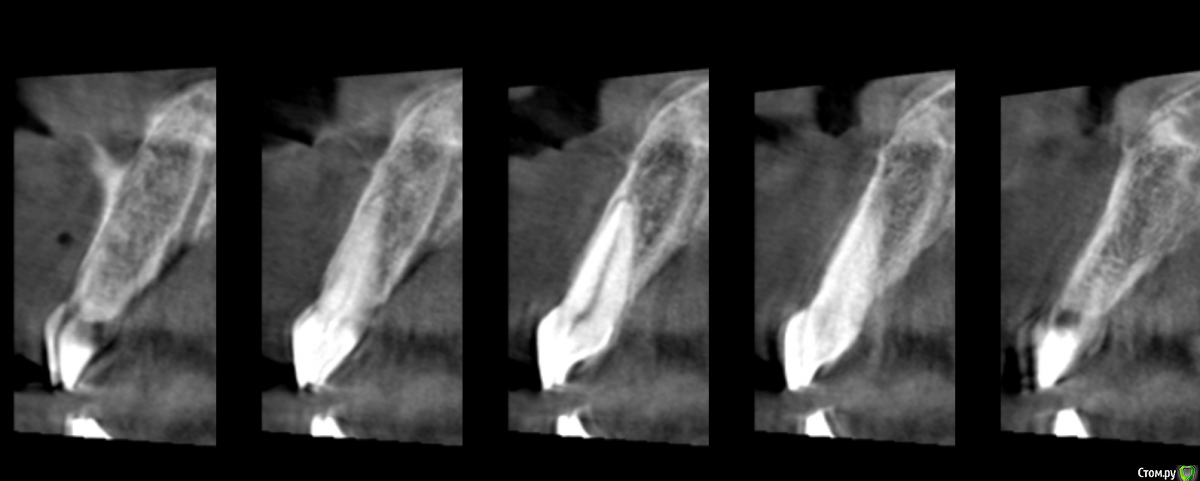

Дмитрий Л. Опубликовано 9 июня, 2018 Поделиться Опубликовано 9 июня, 2018 Я сам решил просто рассечь и удалить эту гадость но честно говоря смушают размеры и плюс случай такой первый раз лишний опыт не помешал бы.Спасибо.Научить чистить зубы.Рассекать смысла большого нет, может сильно кровить.Высечь до кости, бором или фрезой обработать +- милиметр кортикалки и под йодоформным тампоном провести.Гистология.Эндодонтия 21. 2 Ссылка на комментарий

Дмитрий Л. Опубликовано 11 июня, 2018 Поделиться Опубликовано 11 июня, 2018 Зачем? Зачем?! Будет дефект слизистой и оголённая кость. Как бы вы предложили вести такую рану? Как вы считаете, какая этиология эпулида в данном случае? Есть ли причинный зуб? Какой вообще диагноз и лечение вы бы предположили / предложили? Ссылка на комментарий

Irouil Опубликовано 11 июня, 2018 Поделиться Опубликовано 11 июня, 2018 На дворе вроде 21 век, зачем йодоформ? Большой дефект - лоскут, трансплантат, небольшой дефект - мобилизация, самозаживетизация. Я бы перед эндо как минимум провел ЭОД. Ссылка на комментарий